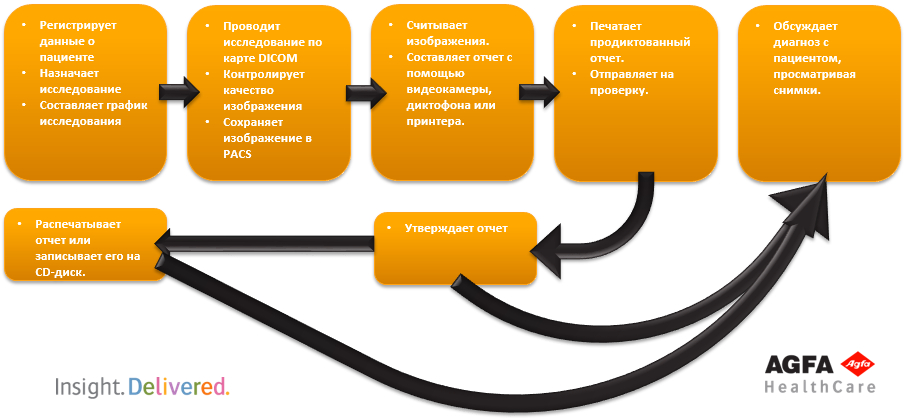

Полный цифровой рабочий процесс для отделения визуализационной диагностики

| Дежурный приёмного отделения | Технолог | Рентгенолог | Фонотипист | Клинический врач |

Рабочий стол технолога